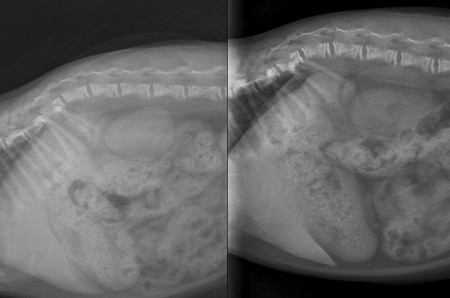

3 month-old Domestic shorthair cat presented for generalized pain. Slight hypocalcemia and hypophosphatemia are noted, whereas other biochemical values are within normal limits.

From a general point of view, we observe:

- a decreased raiopacity of the skeleton and a thinning of the cortex;

- a subtle osseous deformation: curved aspect of long bones, convex aspect of the pelvis, lordosis of the thoracolombar spine;

- a widening of the metaphyses;

- irregular metaphyses;

- narrowed and fragmented epiphyses;

- increased distance between metaphyses and epiphyses;

- flarring and cupping of the metaphyses;

- rosary sign at the level of the costochondral junctions in the rib cage.

Generalized osteopenia associated with a delayed growth.

Radiographic signs consistent with Rickets.